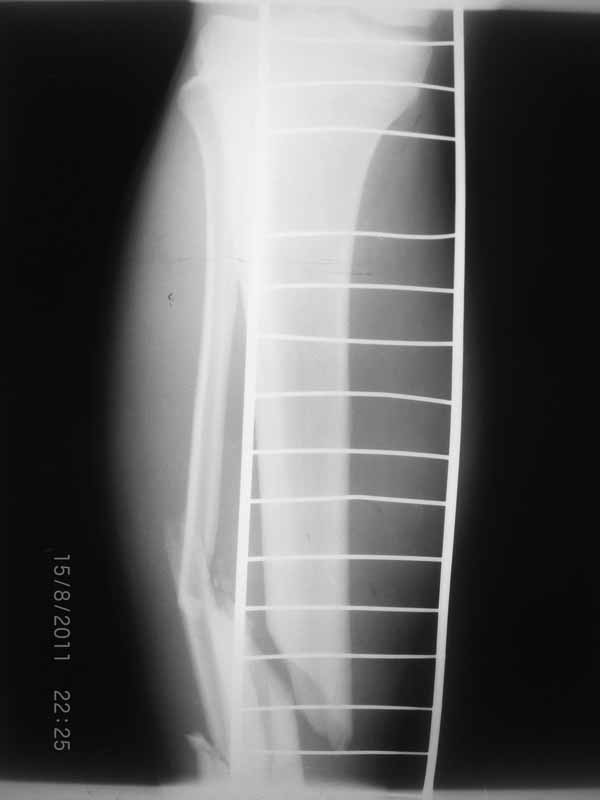

Это гипотрофический ложный сустав. Проблем видится несколько:

1. нарушение трофики в месте перелома.

2. после фиксации в аппарате Илизарова на рентгеногнрамме имеются признаки спицевого остеомиелила. В настоящи момент хотя свищей нет с мая 2011 нет опасно ли фиксировать голень стержнем?

На основании каких признаков Вы решили, что кость мертвая! Имеется гиперпластический ложный сустав, как результат недостаточно стабильной фиксации ан предыдущих этапах лечения. В данном случае необходимо решение следующих вопросов:

Место ложного сустава не выглядит гипертрофическим. Нет разрастания костной мозоли.